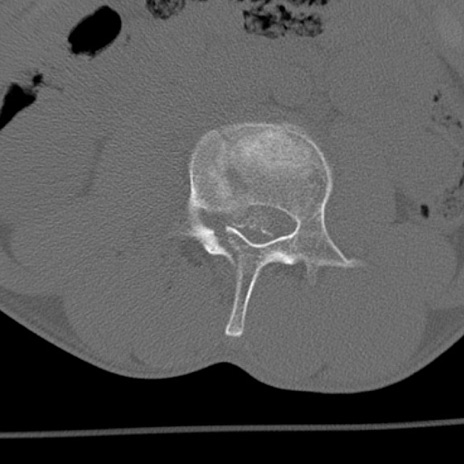

症例3 腰椎CT(横断像)

腰椎CT